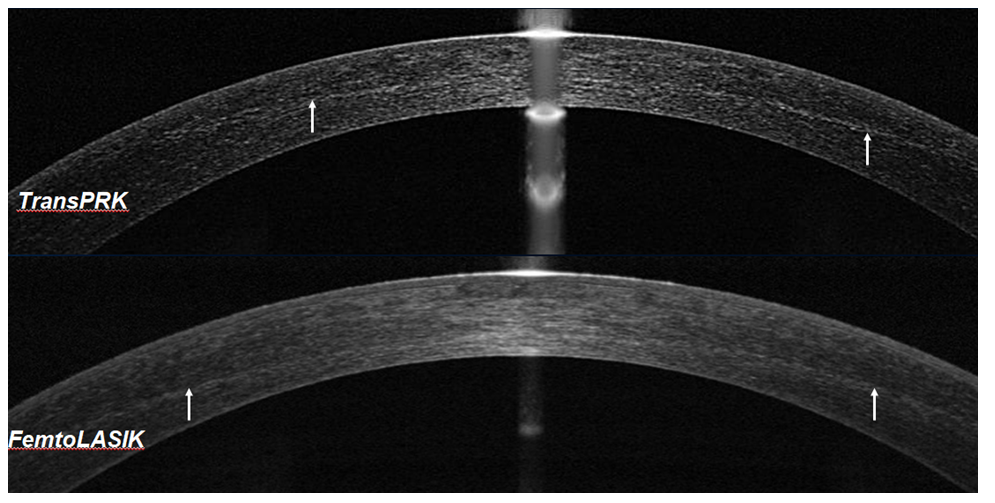

With this photokeratoablation technology, the quality of the ablative surface improved due to the formation of a Bowman-like membrane structure. On OCT of the cornea, such a membrane structure was detected only when its thickness exceeded 5 μm, which corresponded to the resolution of the device (Figure 4). OCT and densitometric studies showed an increase in optical density in the stromal layers adjacent to the ablation zone. In isolated cases, after 3-4 weeks, a gentle demarcation line was revealed (Figure 5). With corneal densitometry, an increase in optical density was observed in the stromal layers adjacent to the ablation zone. With prophylactic laser-induced crosslinking, the elastic properties of the cornea were not impaired. Visual and optical-refractive results of prophylactic crosslinking have been reviewed in previously published works [6,7].

Figure 5:The appearance of a gentle demarcation line a month after the operations TransPRK andFemtoLASIK with riboflavin.

Depending on the pathology of the cornea, the saturation time ranged from 5 to 30 minutes. During therapeutic laser-induced crosslinking, according to OCT and densitometry, all the classic signs of traditional crosslinking were revealed (Figure 7). The stabilization or improvement of visual and optical-refractive indices has been traced for 2.5 years and observations are ongoing.

Dynamic OCT and densitometric studies have shown that the timing of the appearance and reversibility of the demarcation line was similar to those with traditional and accelerated technologies of corneal crosslinking [8-10].In view of the patenting of this technology, specific sub-threshold parameters of laser radiation and the features of scanning the de-epithelialized surface of the cornea are not considered in this article.